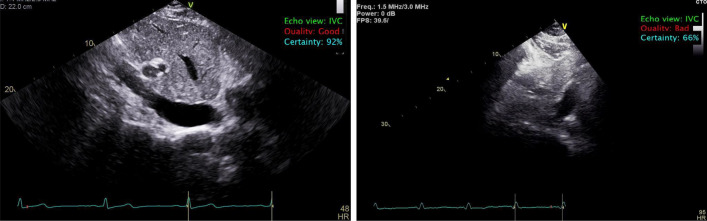

Another important step prior to automated IVC quantification is the quality assessment of the view. Several studies (e.g., [28]) reported that the accurate analysis of echocardiography is hugely dependent on the quality of the images, and that poor-quality images impair echocardiography quantifications. Therefore, we utilized a lightweight algorithm for assessing the quality of the IVC image prior to boundary delineation and thickness quantification. Our quality assessment algorithm achieved an accuracy of 0.94 ± 0.10, a precision of 0.94 ± 0.04, a sensitivity of 0.95 ± 0.09, and f-1 score of 0.95 ± 0.06. Figure 2 shows examples of echocardiography images classified as IVC with good and bad quality.

Fig. 2.

Left: example of good quality IVC view retrieved automatically from a set of other views; right: example of IVC view retrieved automatically from a set of other views and labeled as unusable (bad quality) as the IVC’s boundary is not clear